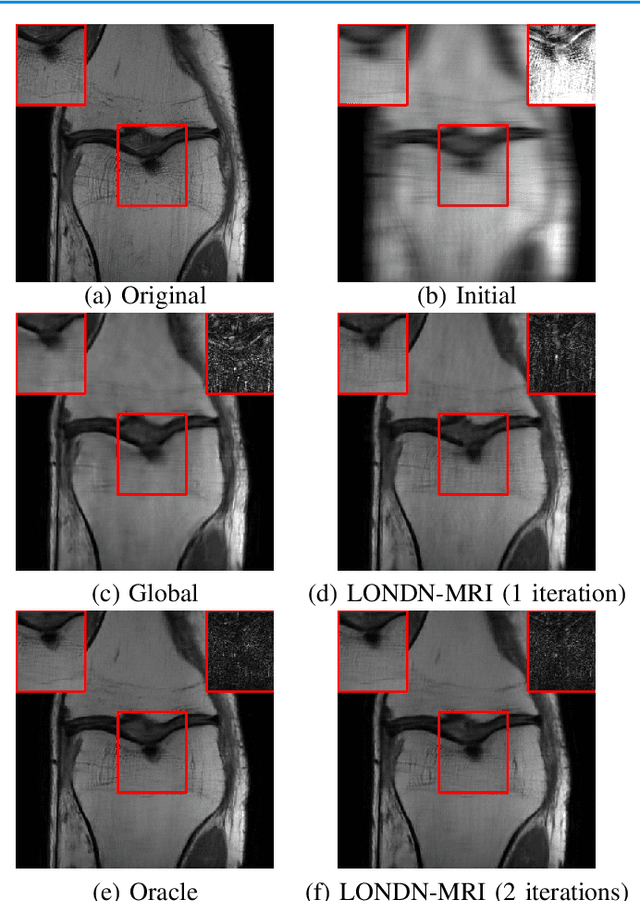

Abstract:Recent medical image reconstruction techniques focus on generating high-quality medical images suitable for clinical use at the lowest possible cost and with the fewest possible adverse effects on patients. Recent works have shown significant promise for reconstructing MR images from sparsely sampled k-space data using deep learning. In this work, we propose a technique that rapidly estimates deep neural networks directly at reconstruction time by fitting them on small adaptively estimated neighborhoods of a training set. In brief, our algorithm alternates between searching for neighbors in a data set that are similar to the test reconstruction, and training a local network on these neighbors followed by updating the test reconstruction. Because our reconstruction model is learned on a dataset that is structurally similar to the image being reconstructed rather than being fit on a large, diverse training set, it is more adaptive to new scans. It can also handle changes in training sets and flexible scan settings, while being relatively fast. Our approach, dubbed LONDN-MRI, was validated on the FastMRI multi-coil knee data set using deep unrolled reconstruction networks. Reconstructions were performed at four fold and eight fold undersampling of k-space with 1D variable-density random phase-encode undersampling masks. Our results demonstrate that our proposed locally-trained method produces higher-quality reconstructions compared to models trained globally on larger datasets.